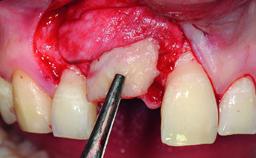

Replacement of an Upper Right Central Incisor with Root Resorption: Ridge Preservation, Delayed Placement of an NC Bone Level Roxolid Implant

A 32-year-old female Caucasian patient with a compromised maxillary right central incisor was referred to us by a general dentist. Her chief complaints were discomfort and mobility of tooth 11 with unsatisfactory esthetics due to discoloration. The patient reported a previous trauma, some years earlier, as the origin of pathology on the afflicted tooth. Anamnesis was negative for any other dental or periodontal pathology in the remaining dentition. The patient did not take any medication and reported to be a light smoker (5–10 cigs/day). She had high esthetic expectations of her treatment. The extraoral examination revealed a high smile line with full exposure of her maxillary teeth and surrounding soft tissue in the area between the second premolars.

Bone Augmentation Horizontal|Simultaneous|Staged

Augmentation Materials Autogenous chips|Xenogenous|Membrane

Soft Tissue Grafting Staged